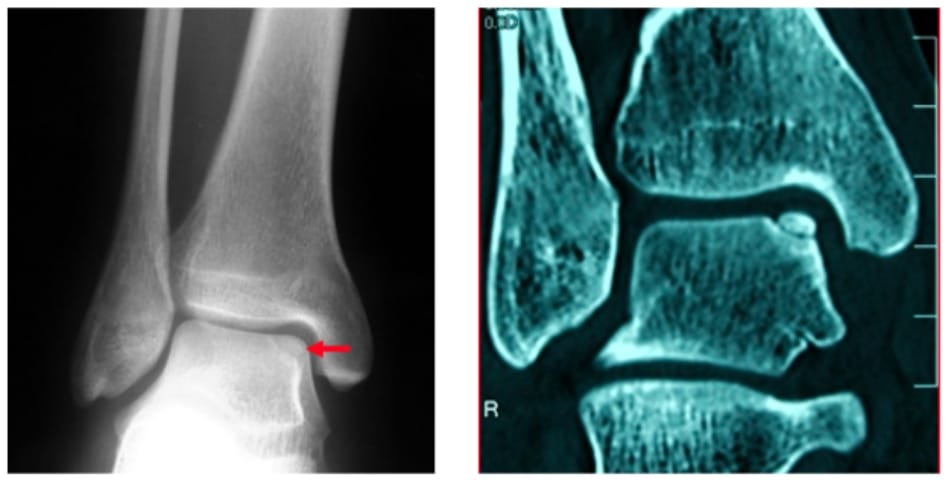

距骨骨軟骨損傷とは足首の捻挫や若年時のスポーツなどが原因で、距骨という足首の骨の一部が傷つく疾患です。

病状の進行状況に応じて手術の方法を決定します。足関節鏡をみながら、針金のようなもので骨に刺激を加えたり、自身の骨を用いて固定したりします。病状が進行している場合には切開手術で膝から骨軟骨を移植することもあります。